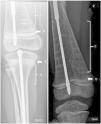

Actualmente reciben tratamiento con denosumab en nuestra unidad otros 2 pacientes con OI: un varón con OI-VI (c.273_283+1del + c.271_279dupGCCCTCTCG) y una niña con OI-III (COL1A1 607G>C). En ambos hemos observado la banda hiperdensa pero no la imagen de «nube de humo» (fig. 2).

Durante el crecimiento, la administración intravenosa de BF da lugar a la aparición de la clásica imagen radiológica en «líneas cebra». Denosumab incrementa la formación ósea generando una banda hiperdensa a nivel de la metáfisis3, sin embargo esta imagen en patrón difuso no había sido descrita con anterioridad, siendo quizás una expresión fenotípica relacionada con mutación específica que porta nuestro paciente.